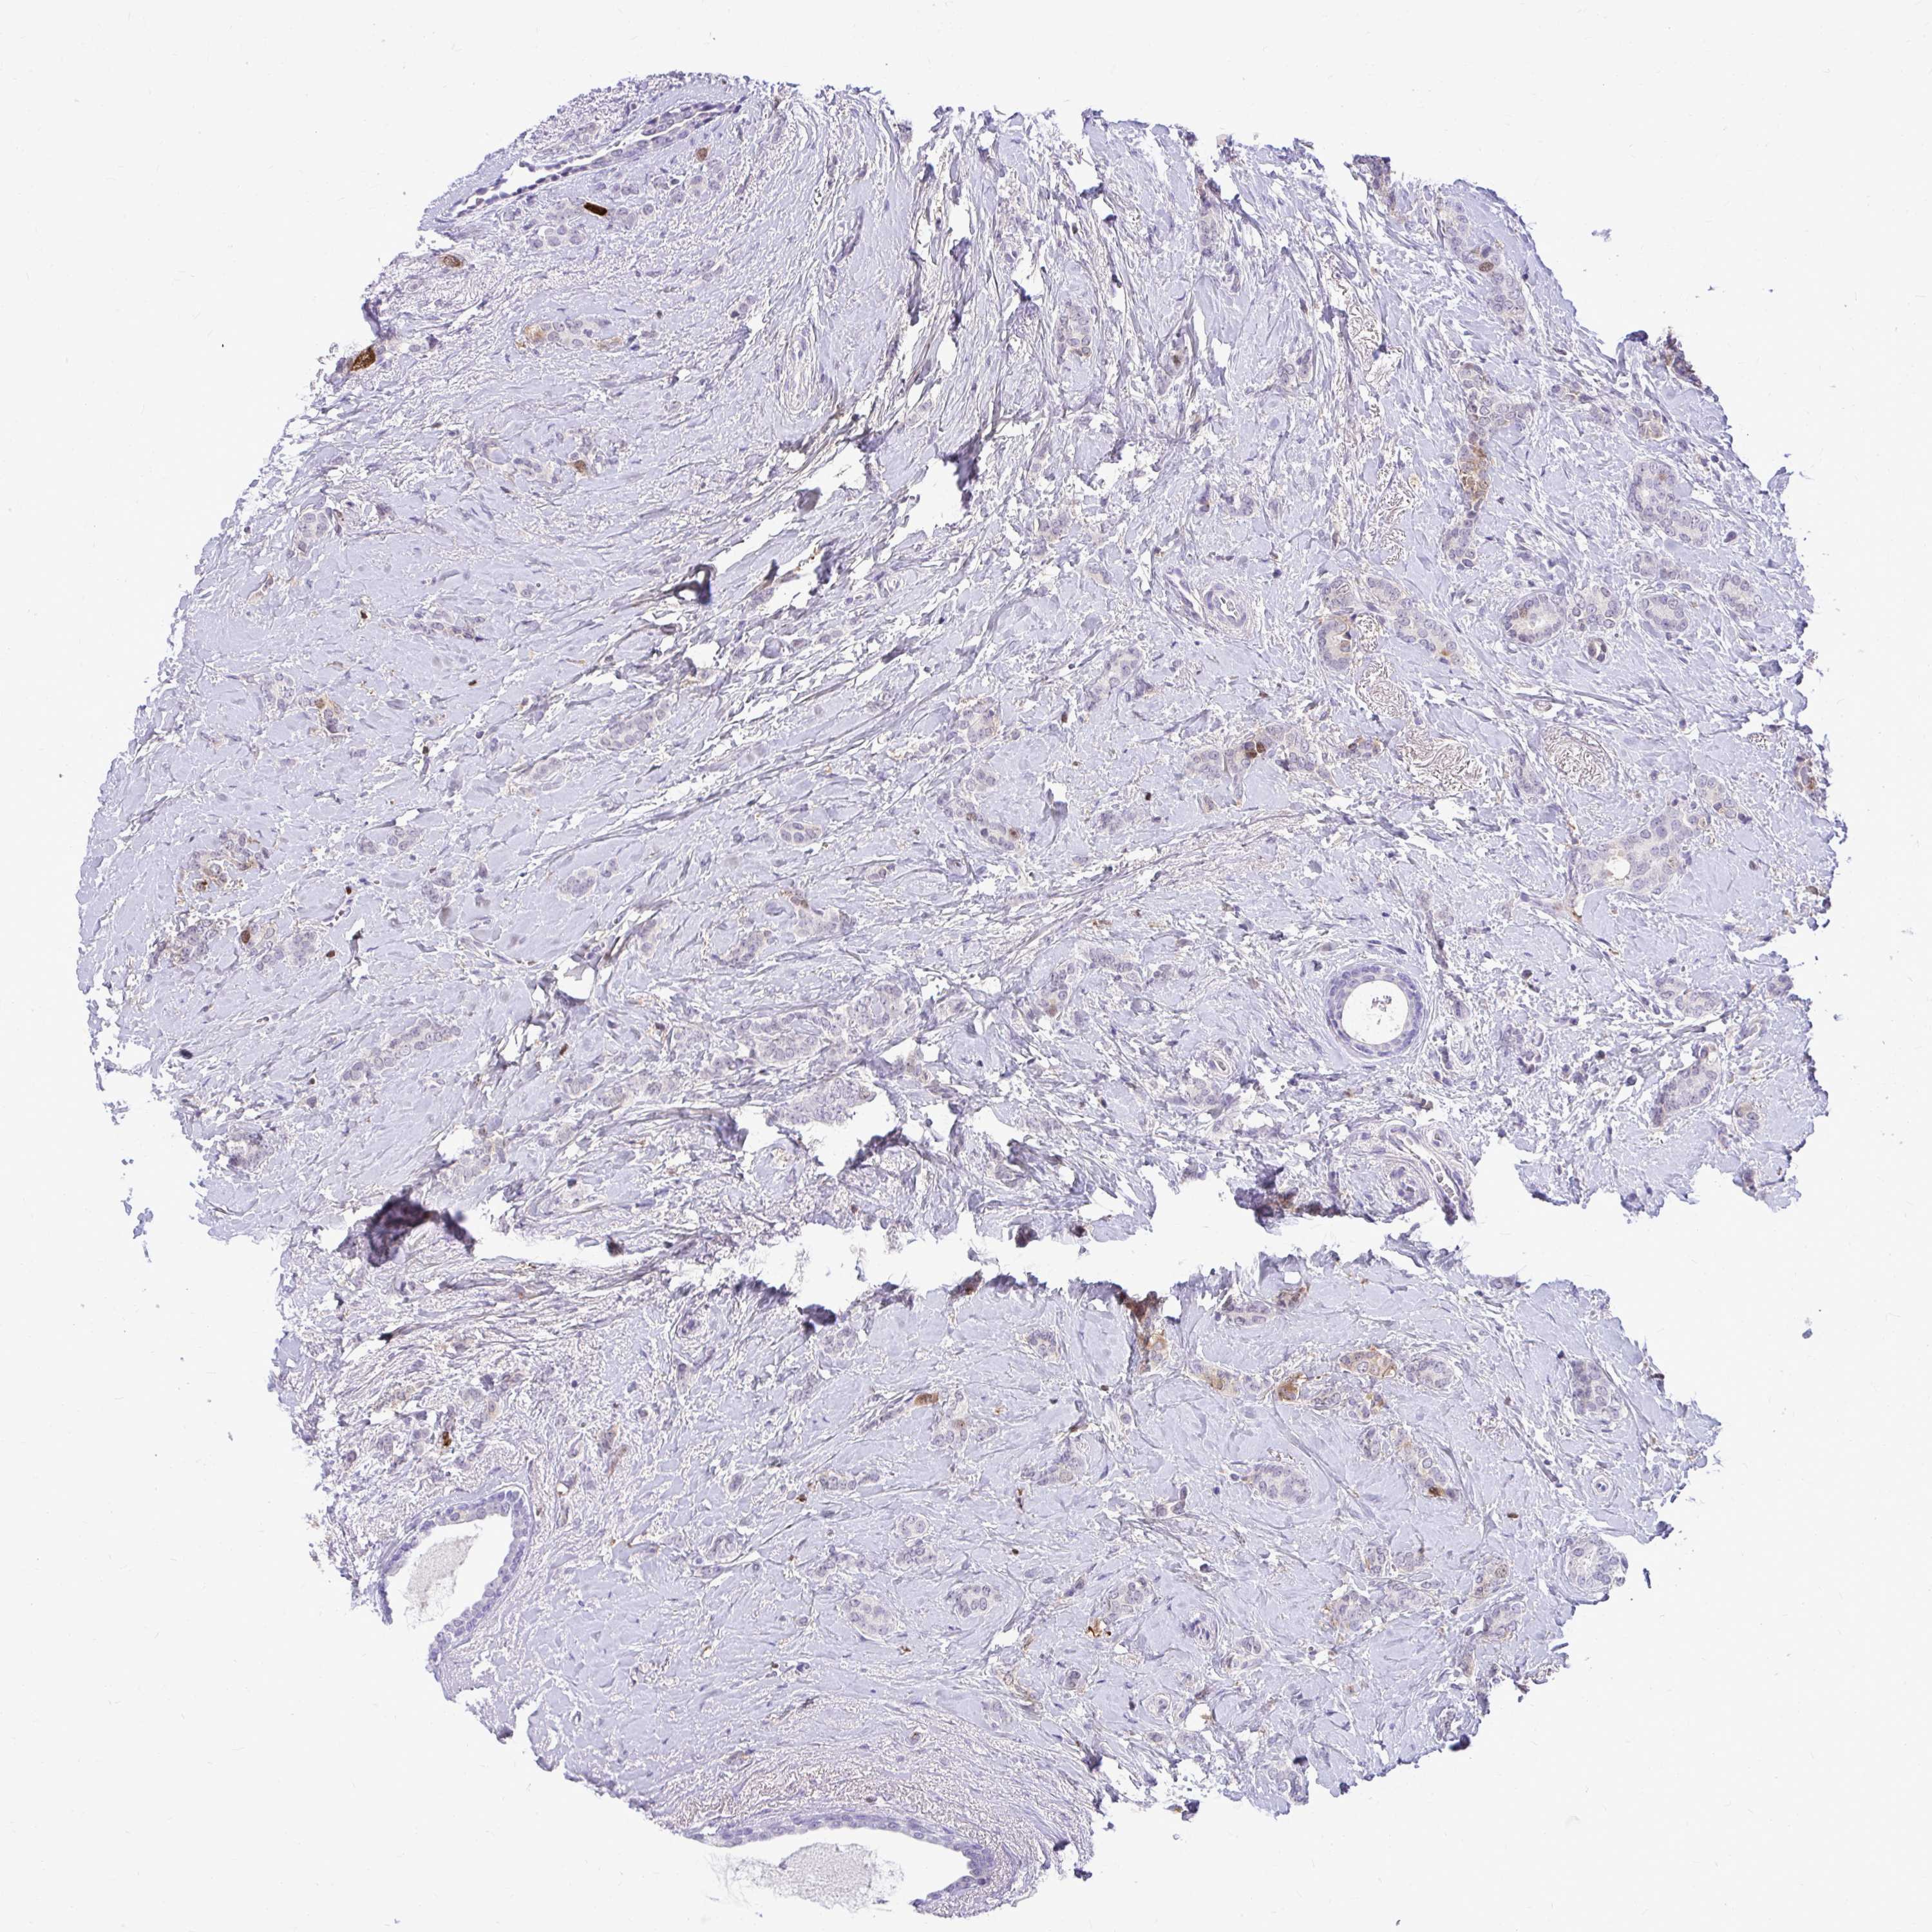

BRCA TCGA BRCA VALIDATION PROTEIN EXPRESSION

ANTIBODIES

AND

VALIDATION